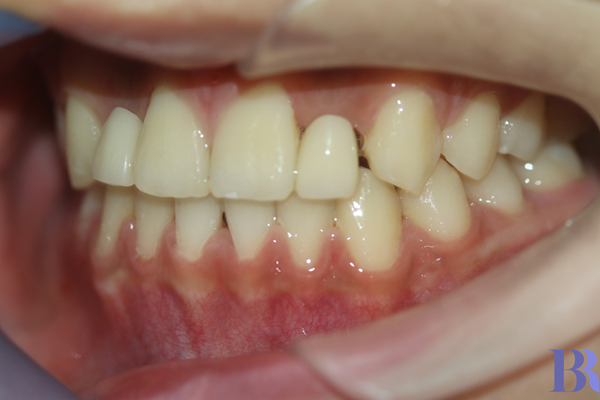

교정 후 오른쪽 모습

반대교합이 잘 해결되었네요.

뿐만 아니라 교합도

굉장히 안정적으로 형성됐습니다.

정말 뿌듯합니다!!! ^^